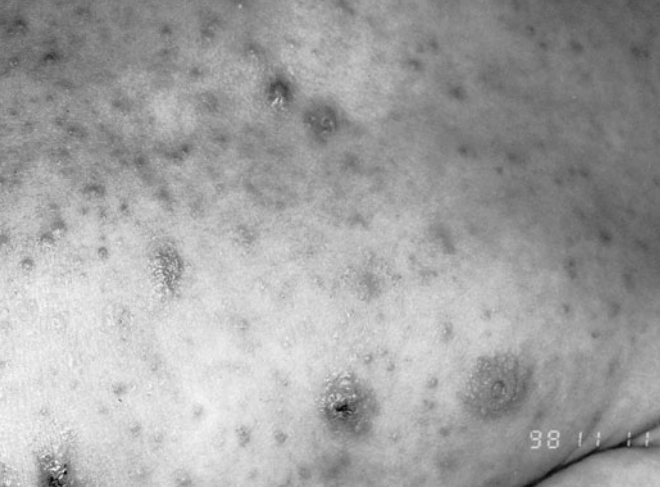

Scabies

path: Scabies is caused by the mite Sarcoptes scabiei var. hominis. Contagious

symptoms

Most older children and adults present with intensely pruritic and threadlike burrows in the interdigital areas, groin, elbows, and ankles; the palms, soles, face, and head are spared.

Infants, however, usually present with bullae and pustules, and the areas spared in adults are often involved in infants. The clinical manifestations closely resemble those of atopic dermatitis.